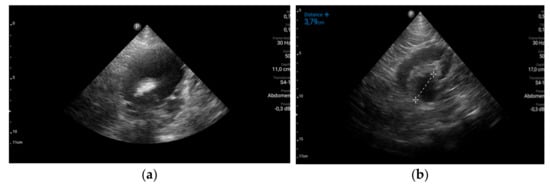

The stage diagnosis was hemorrhagic syndrome precipitated by severe thrombocytopenia. To identify the causes and the consequences of the hemorrhagic syndrome, more laboratory tests and imagistic explorations were performed. Abdominal ultrasound revealed uncomplicated biliary stones and multiple urinary bladder obstructive stones with third degree bilateral hydronephrosis explaining the abdominal pain and renal failure (Figure 2). No visceral hematomas or ascites were detected.

Figure 2. Abdominal ultrasound. (a) Hypogastric transversal section: urinary bladder obstructive stone, 3 cm in diameter and distended urinary bladder; (b) Right flank longitudinal section: third degree hydronephrosis of the right kidney.